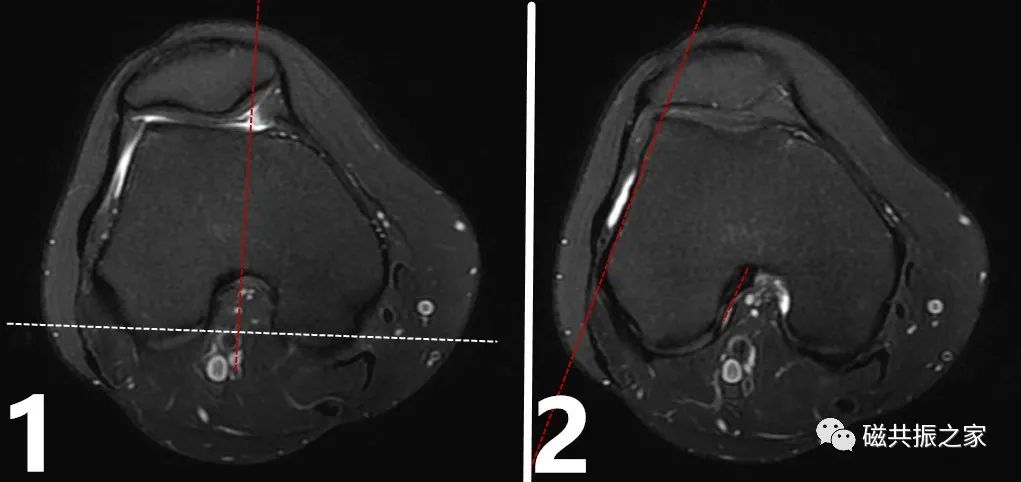

膝关节的扫描基线以股骨内、外髁后缘连线为基准,实际扫描中较常见的矢状面定位主要有两种方式:

图1:垂直于股骨内外髁后缘。

图2:平行于股骨外侧髁前缘。

膝关节扫描定位的差异主要存在于矢状位的定位中,在常规的扫描中建议采用图1的方式定位,该定位方式对90%以上的前交叉韧带都可以得到很好的显示,同时也更利于对半月板及关节软骨的评估。当标准的图1矢状面不足以评估前交叉韧带时,可补充薄层的图2斜矢状面扫描方式。